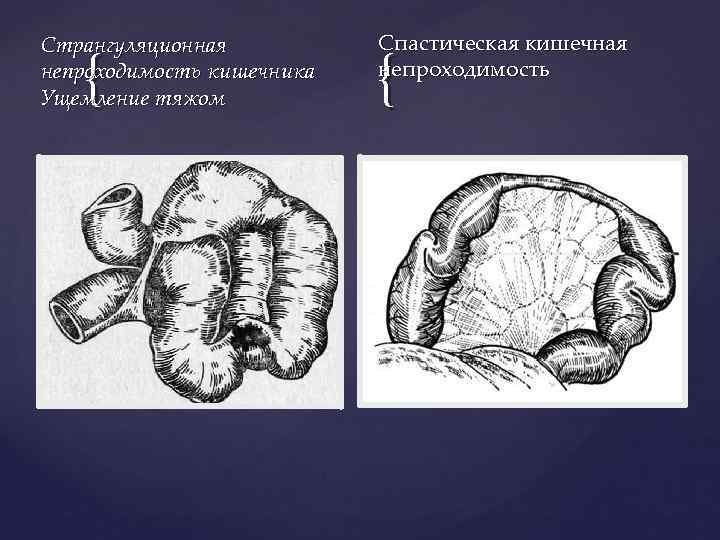

Странгуляцияға ішек бұралуы, байлануы, қысылуы, күрмелуі себеп болады. Обтурациялық түрінде ішек ісікпен, аскаридамен, дәкелі құрғатқыш (операцияда ұмытылған) бітеледі. Қан айналысы онша бұзылмайды. Өйткені шажырқай қысылмайды. Ішек түйілуінің келесі себебі инвагинация - ішекке ішек еніп оның бітелуіне қоса шажырқайдың қысылып, қан айналысы бұзылуы байқалатындығынан илеустің бұл түрінде обтурация және странгуляция қоса байқалады. Ішектің қабырғасының тегіс етінің әлсізденуіне байланысты кездесетін ішек түйілуі динамикалық деп аталады. Илеустің бұл түрін тырысқан және салды деп екіге бөледі. Спастикалық түрі - ішек қабырғасының тырысуынан оның өзегі тарылуымен байланысты болса, паралитикалық илеусте ішек созылған, өзегі кеңіген, оның тонусы - қозғалуы нашарланған.

Странгуляциялық ішек өтімсіздігі

г) Бұралу (volvulus) - ішек өзінің түбірінде айналып бұралады. Бұралу ішектің ең қозғалғыш бөліктерінде ащы ішек пен сигма ішегінде кездеседі. Кан айналысының тоқтауы және ішек түйілуі бұралу мөлшеріне байланысты. Ішектің 1800 бұралуы ішек түйілуіне әкелмейді. 270 -3800 бұралу ішекті және шажырқай қан тамырларын толық бітеп, тез арада ішек гангренасына әкеледі. д) Жабысқақтар және тыртықтар - ішектегі қабыну үрдісінен және операциядан соң пайда болады. е) Күрмелу (Nodus) - странгуляциялық ішек түйілуінің ең ауыр түрі. Күрмелу ащы ішек арасында, немесе ащы және тоқ ішек арасында пайда болады. Бұндай науқастар 12 сағат арасында өліп кетуі мүмкін. Бұл байланған, күрмелген ішектің шапшаң гангренаға шалдығуымен байланысты. Күрмелуге ішектің көп бөлімінің қатынасуы күшті экссудацияға, шокке соғады. Егер ішектің көп бөлшегі күрмелсе метеоризм шамалы. Ішек күрмелуіне ұшырағандардың өлімі 40 -50% жетеді.